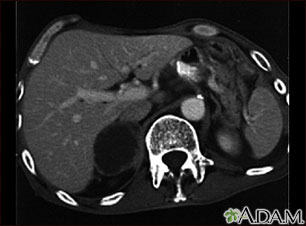

This CT scan of the upper abdomen shows an adrenal metastasis (spreading of a tumor to the adrenal gland, above the kidney) in a person with lung cancer.